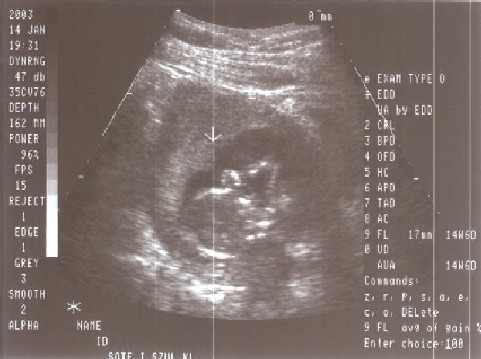

Ez az első fotó amit rólam készítettek. Itt még nagyon kicsi voltam, a kezem és a fejem látszik talán:

Ez a kép is még anyuci pocakjában készült rólam 2003. április 14-én. Itt profilból látszódom: